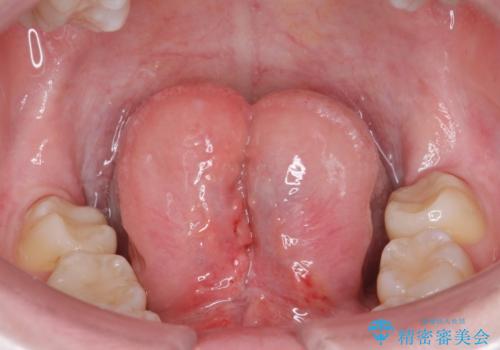

[舌小帯の形成術] 舌の動きが悪い 滑舌を改善したい!

滑舌の改善 舌小帯の形成術